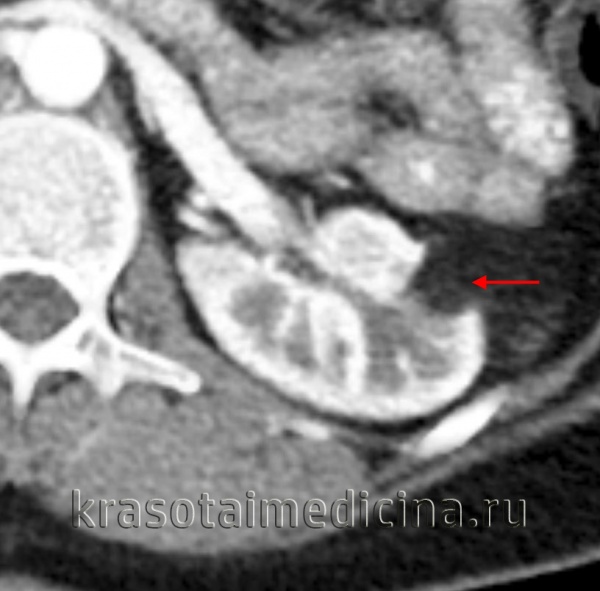

При МСКТ в нижнем сегменте правой почки экстраренально определяется округлое образование диаметром 3 см, неоднородной повышенной плотности, с четкими ровными контурами, не накапливающее контрастный препарат (плотность до контрастирования 63 ед.Н., после контрастирования 64 ед.Н) - осложненная киста (рис. 2). В верхнем сегменте левой почки киста 1,5 см, в среднем ангиомиолипома до 1,8 см в диаметре.

Рис. 2. Мультиспиральная компьютерная томография (МСКТ) - стрелкой указано образование в нижнем сегменте правой почки.